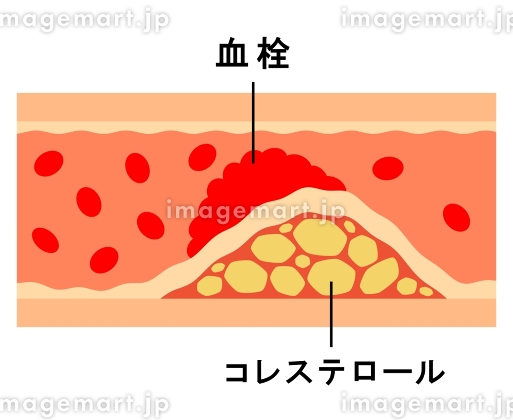

血栓症」のイラスト素材・ベクター画像 - イメージマートimagemart。

血栓症」のイラスト素材・ベクター画像 - イメージマートimagemart。

正常な血管と血栓ができた血管 イラスト素材5358451- フォトライブラリ。

血栓症」のイラスト素材・ベクター画像 - イメージマートimagemart。

血栓症」のイラスト素材・ベクター画像 - イメージマートimagemart。

血栓ができている血管 イラスト素材6665451- フォトライブラリ。